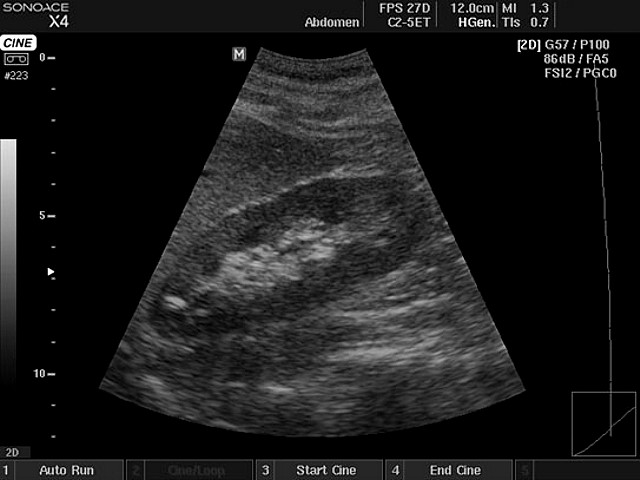

Aceste pietre au fost eliminate de către un pacient (Gafincu G.), care a urmat tratamentul cu Renoregim timp de două luni și jumătate și care a fost diagnosticat cu pietre de 25-30mm

În urma diagnosticului (rinichi cu  polilitiază de dimensiuni între 20 și 30mm) pacientul a fost îndrumat spre clinica de chirurgie Fundeni pentru operație clasică dată fiind multitudinea pietrelor raspândite în tot rinichiul stâng